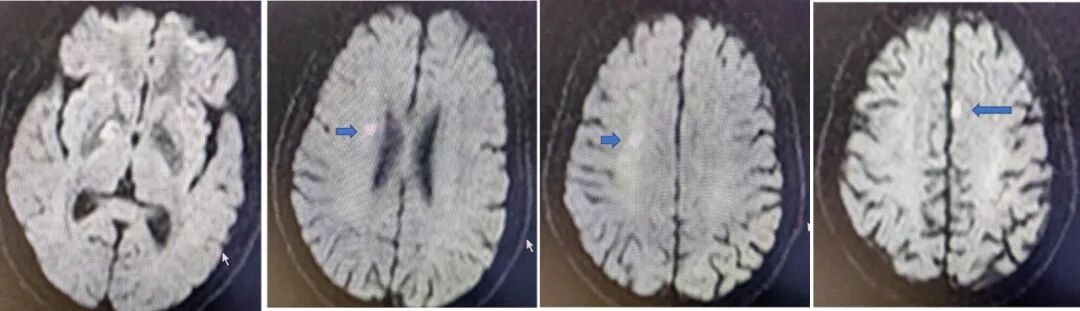

入院影像检查

导丝怎么扩【载药时代 球扩天下】NOVA DES®颅内药物洗脱支架在大脑中动脉重度狭窄的应用二例!_https://www.jmylbn.com_新闻资讯_第22张

MRA

重要影像结论:右侧大脑中动脉M1段局限性狭窄。

导丝怎么扩【载药时代 球扩天下】NOVA DES®颅内药物洗脱支架在大脑中动脉重度狭窄的应用二例!_https://www.jmylbn.com_新闻资讯_第23张

DWI

重要影像结论:右侧额颞枕顶叶多发急性期脑梗死灶。